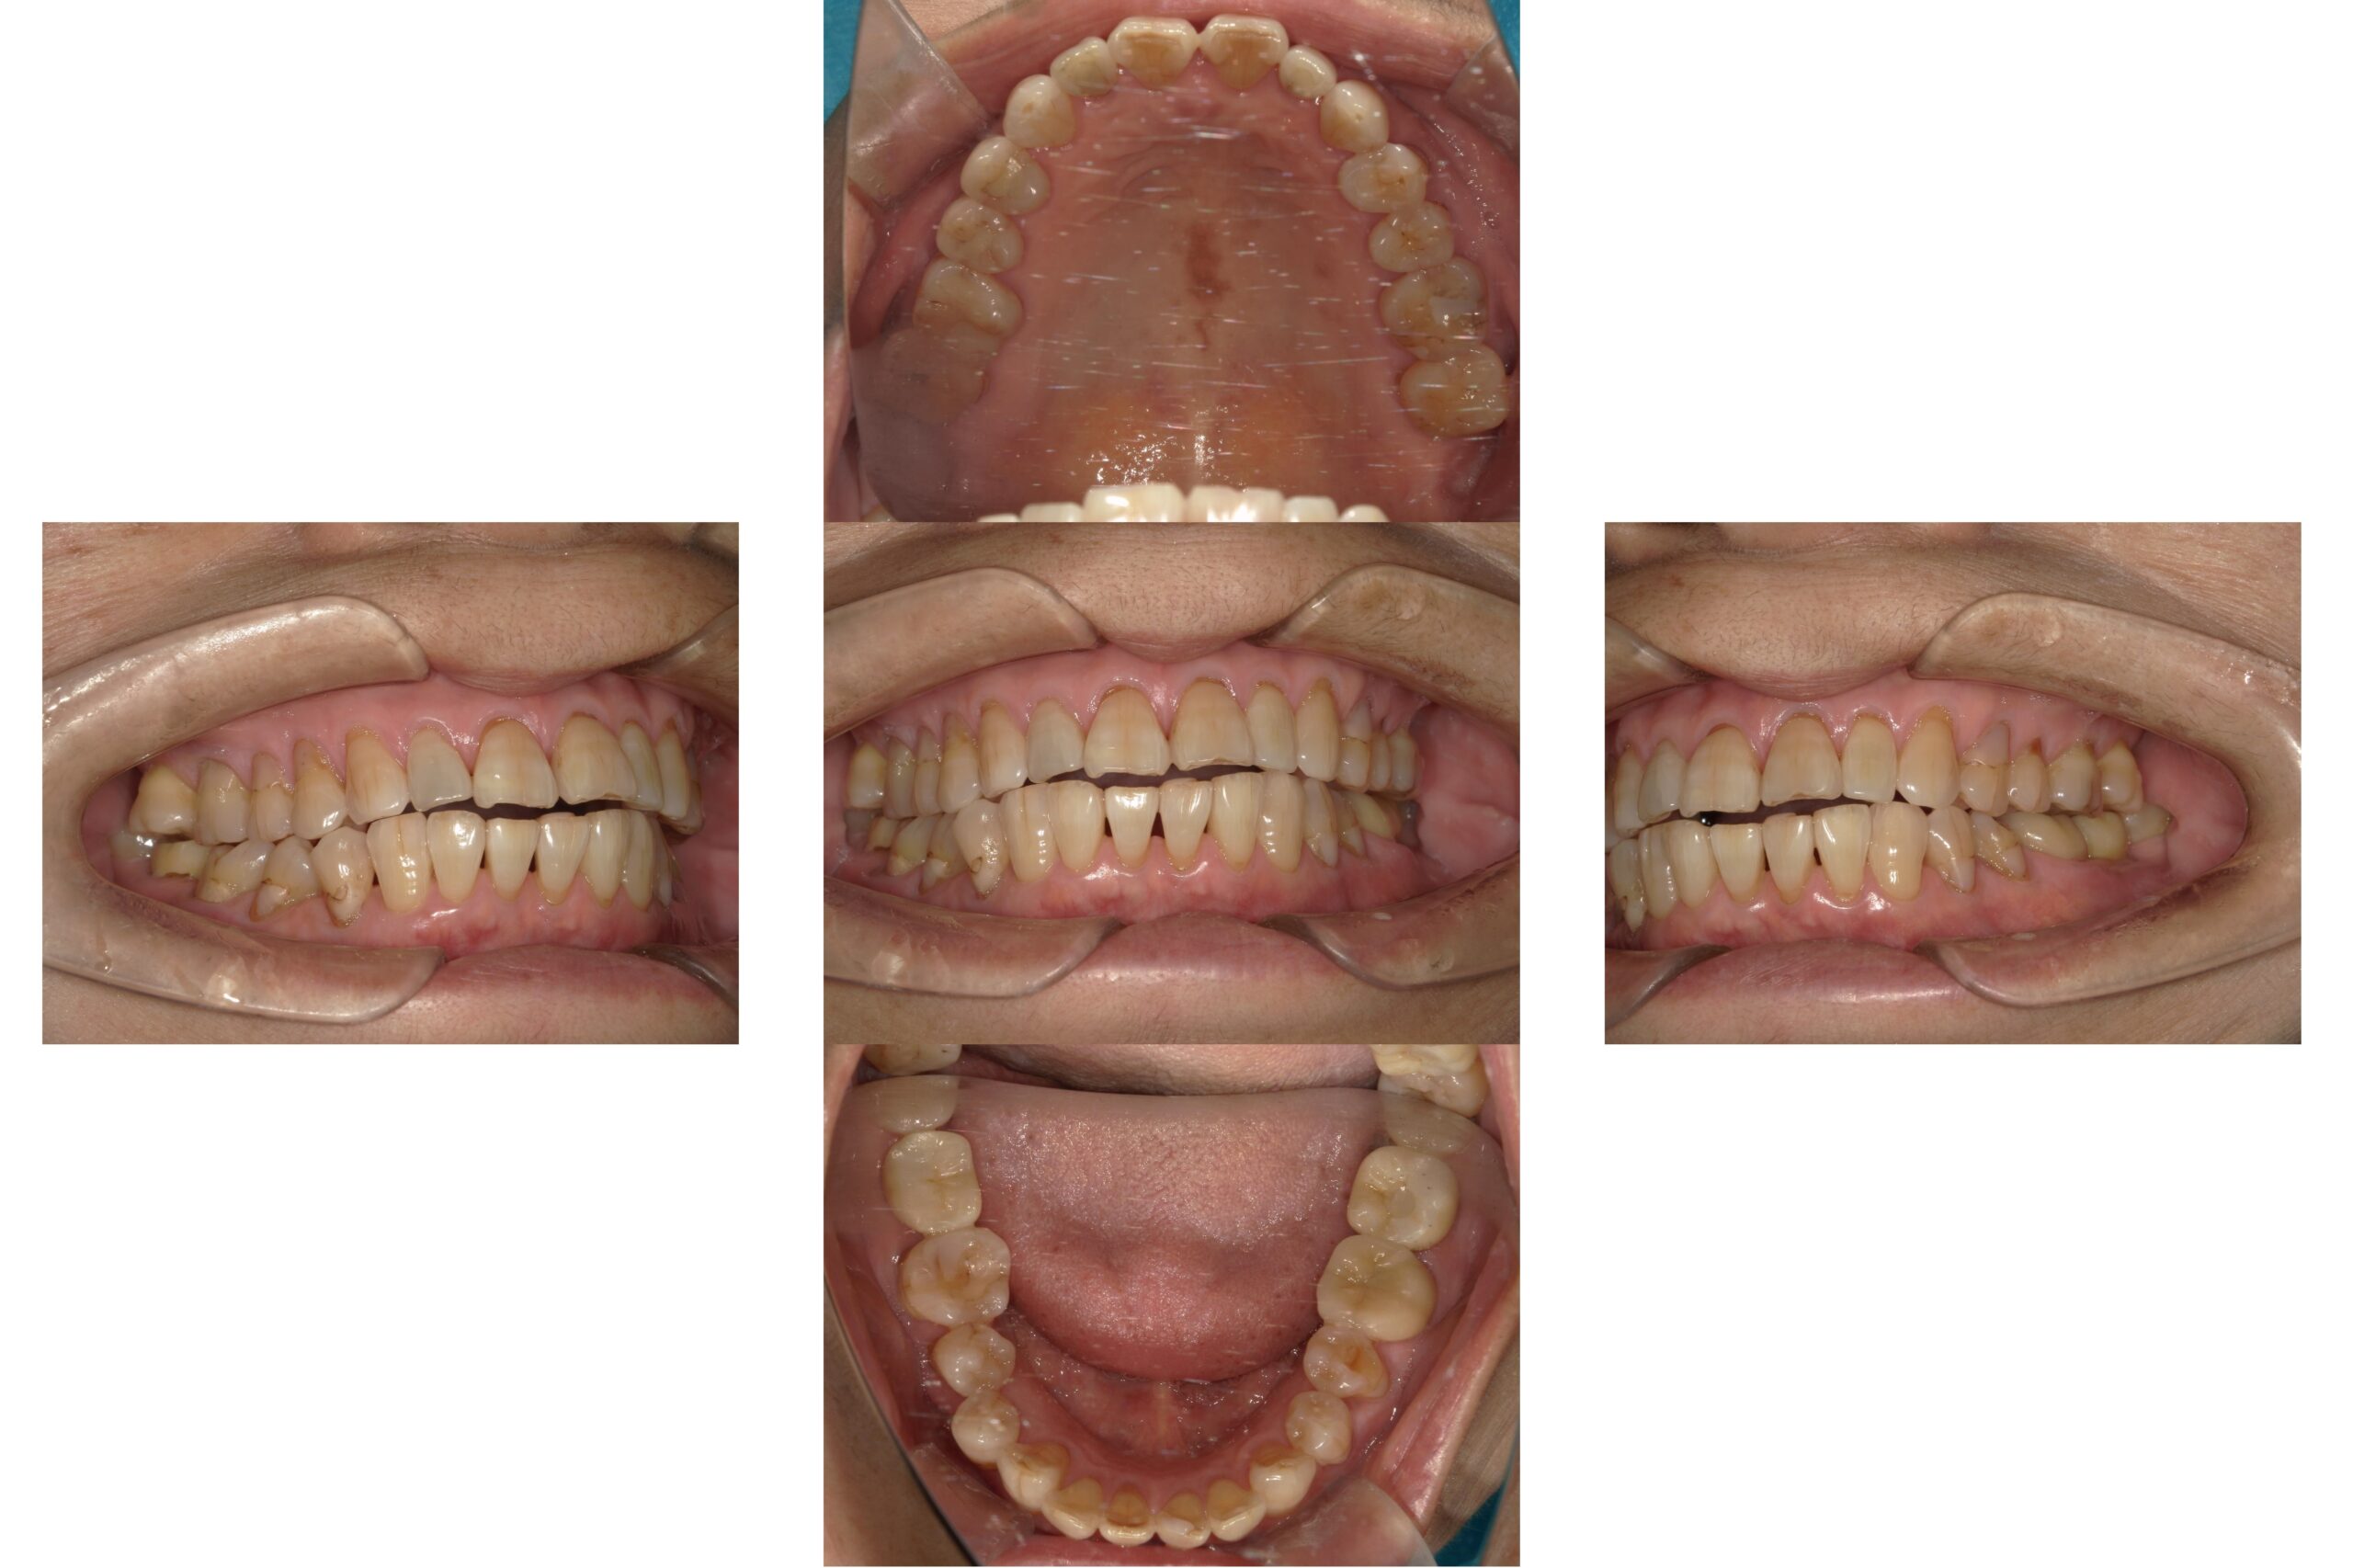

八重歯のマウスピース矯正治療

Before

After

年齢

16歳

主訴

八重歯が気になる。

治療期間

1年

治療費

990,000円(保定装置含む)

概要

八重歯が気になり人前であまり笑顔を見せれない。

唇が閉じにくいこともあり、口の中が乾燥していることがある。

矯正治療が終わり笑顔にも自信を持つことができ、噛み合わせも整ったことで審美的にも機能的にも満足されています。